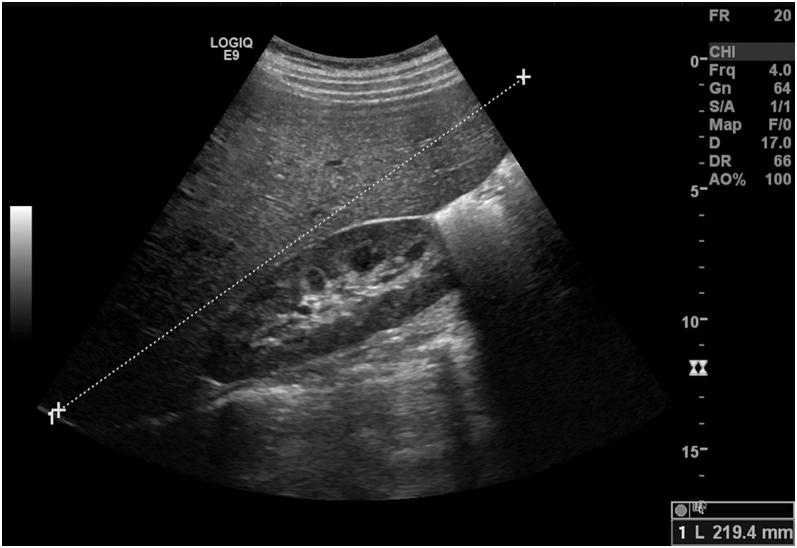

Mauriac syndrome is a rare complication in patients with type 1 diabetes. It presents with poor glycemic control and hepatomegaly due to extensive liver glycogen deposition. Whether behavioral or genetic factors play key roles in its pathophysiology remains a subject of debate. We present the case of a 19-year-old woman with poorly controlled type 1 diabetes mellitus and persistently elevated liver enzymes who arrived at the emergency department with diabetic ketoacidosis and hepatomegaly. Blood tests revealed the absence of an associated viral or autoimmune liver disease. Transient liver elastography showed moderate steatosis. Liver biopsy results were consistent with glycogen hepatopathy. Sequencing of genes associated with glycogen storage diseases revealed no pathogenic variants, supporting a non-genetic mechanism for Mauriac syndrome. Insulin regimen and dietary plan were reviewed. Distinction of glycogenic hepatopathy from metabolic dysfunction-associated fatty liver disease is often difficult and frequently only possible through liver biopsy. An accurate diagnosis of Mauriac syndrome carries important prognostic information, as associated hepatomegaly tends to regress through optimization of glycemic control.

Mauriac综合征是1型糖尿病患者中一种罕见的并发症。它表现为血糖控制不佳以及由于肝脏广泛糖原沉积导致的肝肿大。行为因素或遗传因素在其病理生理学中是否起关键作用仍是一个有争议的话题。我们报告了一例19岁1型糖尿病控制不佳且肝酶持续升高的女性患者,她因糖尿病酮症酸中毒和肝肿大就诊于急诊科。血液检查显示不存在相关的病毒性或自身免疫性肝病。瞬时弹性成像显示中度脂肪变性。肝活检结果与糖原性肝病一致。与糖原贮积病相关基因的测序未发现致病变异,支持Mauriac综合征的非遗传机制。对胰岛素治疗方案和饮食计划进行了评估。糖原性肝病与代谢功能障碍相关脂肪性肝病的鉴别通常很困难,往往只能通过肝活检来实现。准确诊断Mauriac综合征具有重要的预后信息,因为通过优化血糖控制,相关的肝肿大往往会消退。